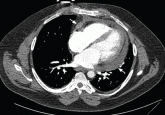

ArticleCardiac tamponade: 12 pearls in diagnosis and managementAuthor:William A. Schiavone, DO, FACCPublish date: February 1, 2013Tamponade shares symptoms and signs with other, more common diseases. Consider it when the patient has chest trauma or a chronic medical illness th...Read More